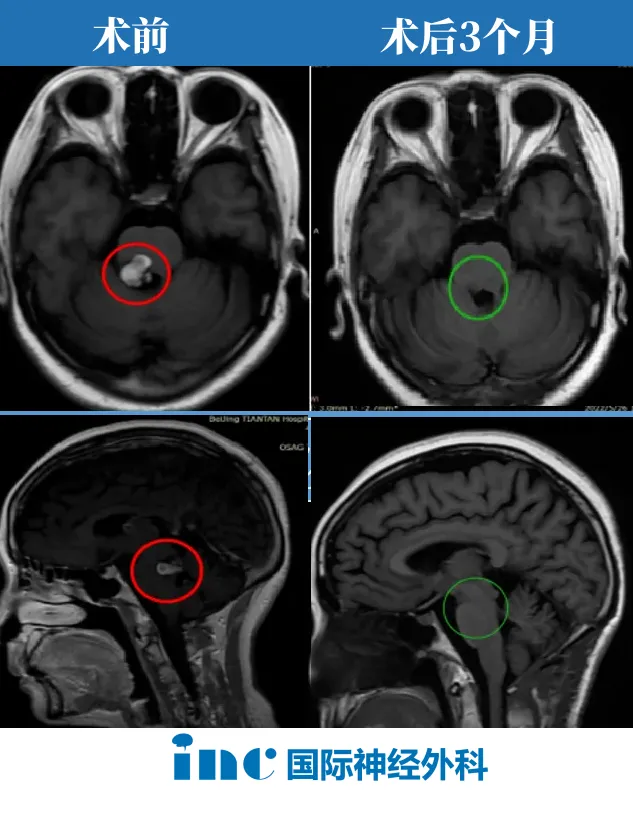

小雨在距离那场开颅术后已经安稳度过了3个月。当初,由巴教授主刀,他的海绵状血管瘤得到全切,才换来如今的正常生活。这3个月以来,他积极康复,如愿以偿回到校园,甚至还拥有了一辆...